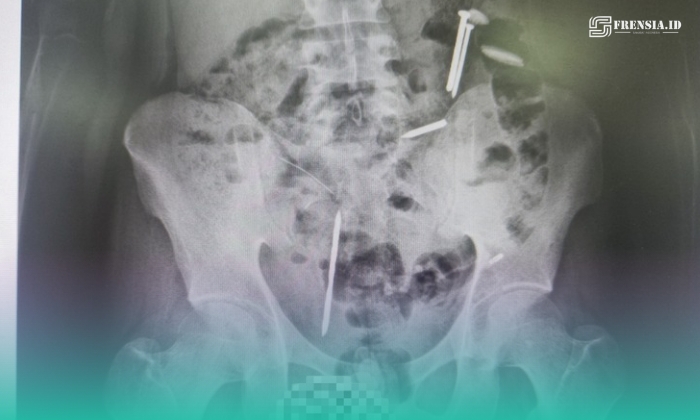

Dari hasil foto rontgen, benda asing itu berada di sekitar perut.

Hasil pemeriksaan tersebut, tim medis menemukan beberapa benda asing di dalam tubuh pasien, di antaranya dua benda menyerupai paku, tiga benda logam lainnya, serta gumpalan berwarna hitam yang belum dapat diidentifikasi secara pasti.

“Jadi tadi saat proses medical check-up, seperti biasa dilakukan rontgen. Dari situ ditemukan benda-benda asing di dalam tubuhnya, bahkan ada juga yang berwarna hitam, kami belum bisa memastikan itu apa, apakah gumpalan darah atau benda lain,” kata Roni saat dikonfirmasi melalui telepon, pada Rabu (8/4/2026) malam.